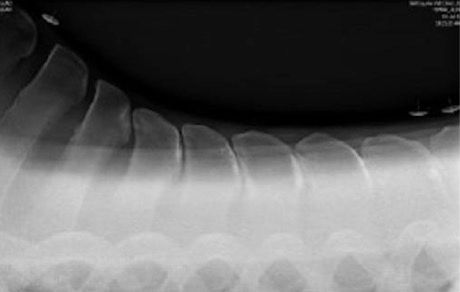

The x-rays below show no gaps in places, so every time this particular horse, has a rider's weight on those areas shown, are asked to turn on a circle or work or simply just carry a rider they probably will feel quite a bit of pain and therefore will show signs of that pain.